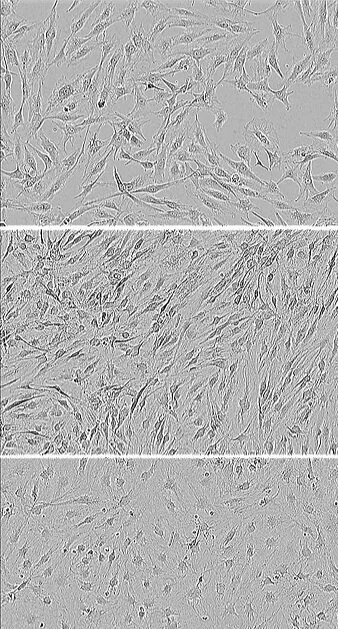

About the image: human hair follicle-derived neuronal precursor cells at different stages of S2N in vitro differentiation.

S2N has developed a proprietary method for isolating, enriching and expanding these cells - termed hair follicle-derived neuroprecursors (HFNs).

Unlike induced pluripotential stem cells, HFN require no genetic modification and are unipotent - they only develop into neurons.